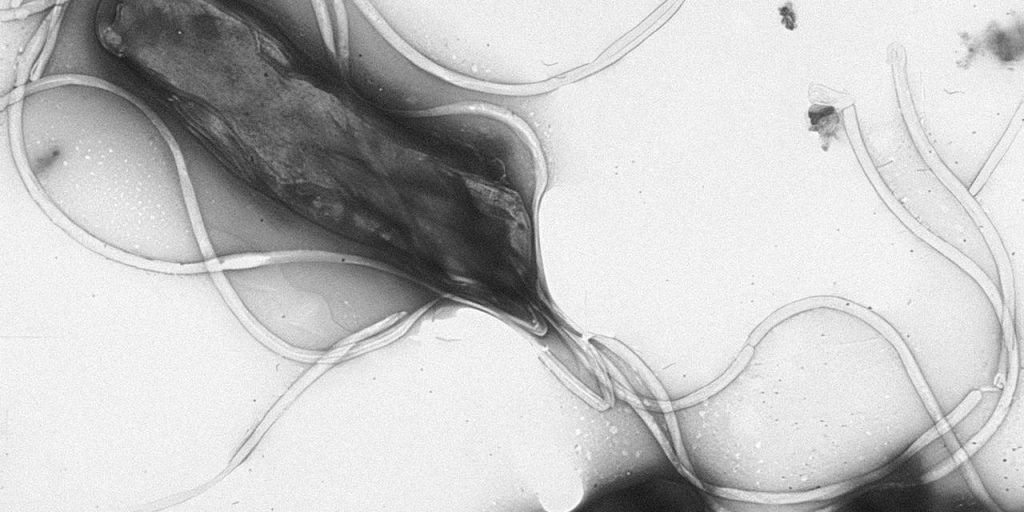

По словам врача, часто к раку желудка приводят воспаления слизистой оболочки этого органа. «Наиболее изученным фактором риска является инфекция Helicobacter pylori, которая может приводить к формированию атрофического гастрита, кишечной метаплазии и другим предраковым изменениям», — предупредил Бамматов.